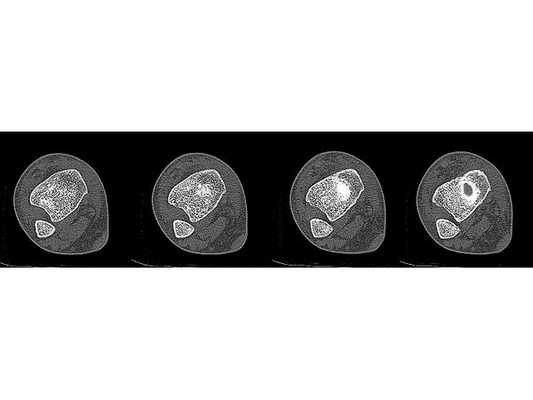

- Компьютерная томография правой голени.

Закрытый оскольчатый перелом внутренней лодыжки правой голени со смещением отломков. Закрытый перелом верхней трети малоберцовой кости правой голени. Повреждение дистального межберцового синдесмоза ( соединения большеберцовой и малоберцовой костей) . Подвывих стопы кнаружи (Maisonneuve-type fracture).

После обследования и уменьшения отёка мягких тканей на четвёртые сутки с момента травмы больному проведено оперативное вмешательство. Под спинномозговой анестезией выполнена открытая репозиция перелома внутренней лодыжки правой голени спицами и стягивающей проволочной петлёй, фиксация дистального межберцового синдесмоза стягивающей петлёй с упорными металлическими площадками.